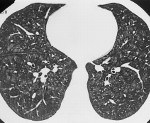

Методы лучевой диагностики имеют вспомогательное значение. Специфичных для биссиноза рентгенологических признаков не существует. Рентгенография и КТ органов грудной клетки помогают обнаружить наличие бронхоэктазов, эмфиземы и других лёгочных осложнений. Определение общего и специфического IgЕ, прик-тесты позволяют выявить сенсибилизацию к пыльце, продуктам питания, бытовым и эпидермальным аллергенам и отличить биссиноз от бронхиальной астмы. Степень поражения правых отделов сердца определяется с помощью эхокардиографии.